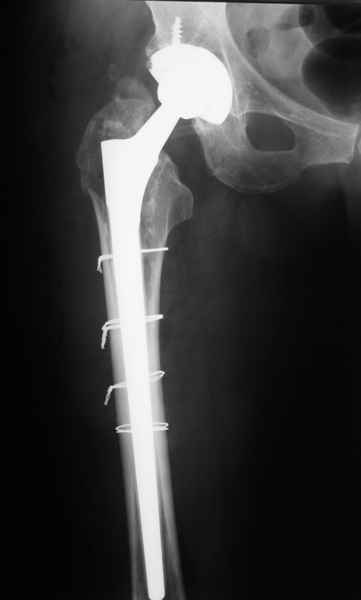

Уважаемые коллеги, продолжая дискуссию, начатую на "Вреденовских чтениях", хочу сказать, что принципиально сущестует два возможных варианта лечения.

1.Остеосинтез на ножке. Мне кажется, что применительно к этому случаю малоперспективный вариант. Синтез хорош, когда можно его выполнить в малоинвазивном исполнении и достигнуть стабильности. Действительно, если ножка б/цементной фиксации после этого не будет иметь фиксации, то ревизия не будет иметь проблем. В представленном случае стабильность синтеза сомнительная, а проведение доп.иммобилизации приведет к контрактуре суставов.

2. Применение ножки дистальной фиксации, мы отдаем предпочтение ножке Вагнера с фиксацией проксимального отдела на ножке. Более травматичное вмешательство, но при стабильной фиксации ножки реабилитация идет в обычном режиме.

Хочется показать два подобных случая, П-ка З. 72 лет и п-т Г. 80 лет. Сразу принимаю замечание, что это были ножки цементной фиксации, просто под руками не было бесцементника.